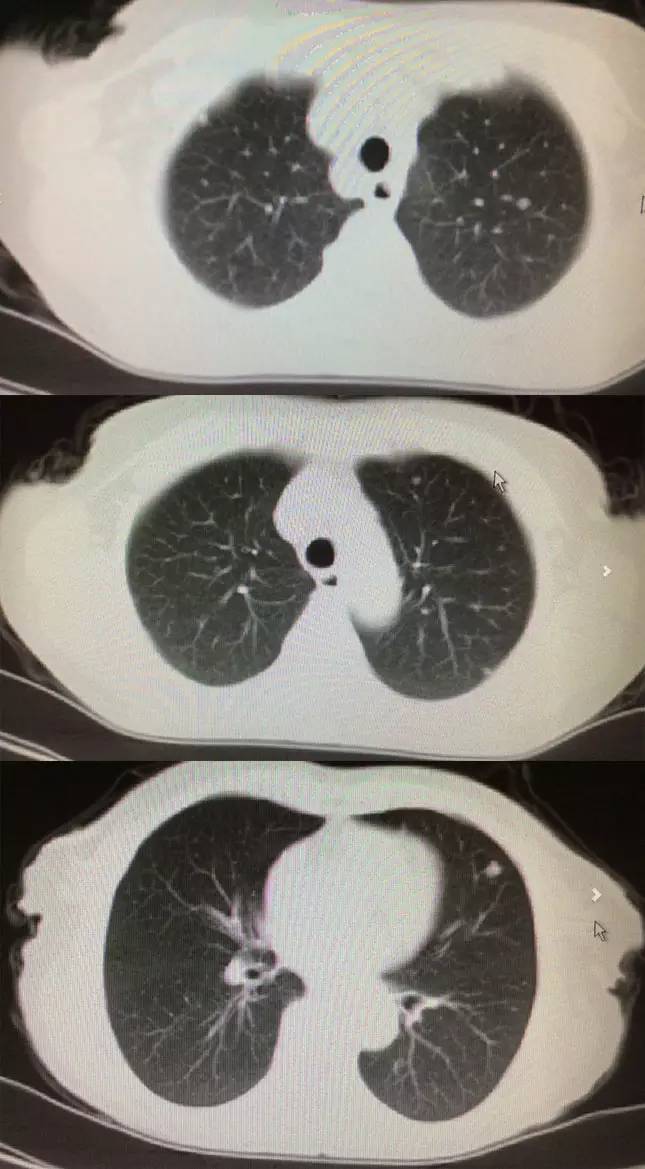

胸部CT:双肺出现多发高密度结节。

4、肺转移:从CT来看双肺多发小结节,考虑转移可能,建议对比既往CT,一方面是评估原来是否有病灶,另一方面评估转移灶倍增时间,即转移肿瘤的生长速度。